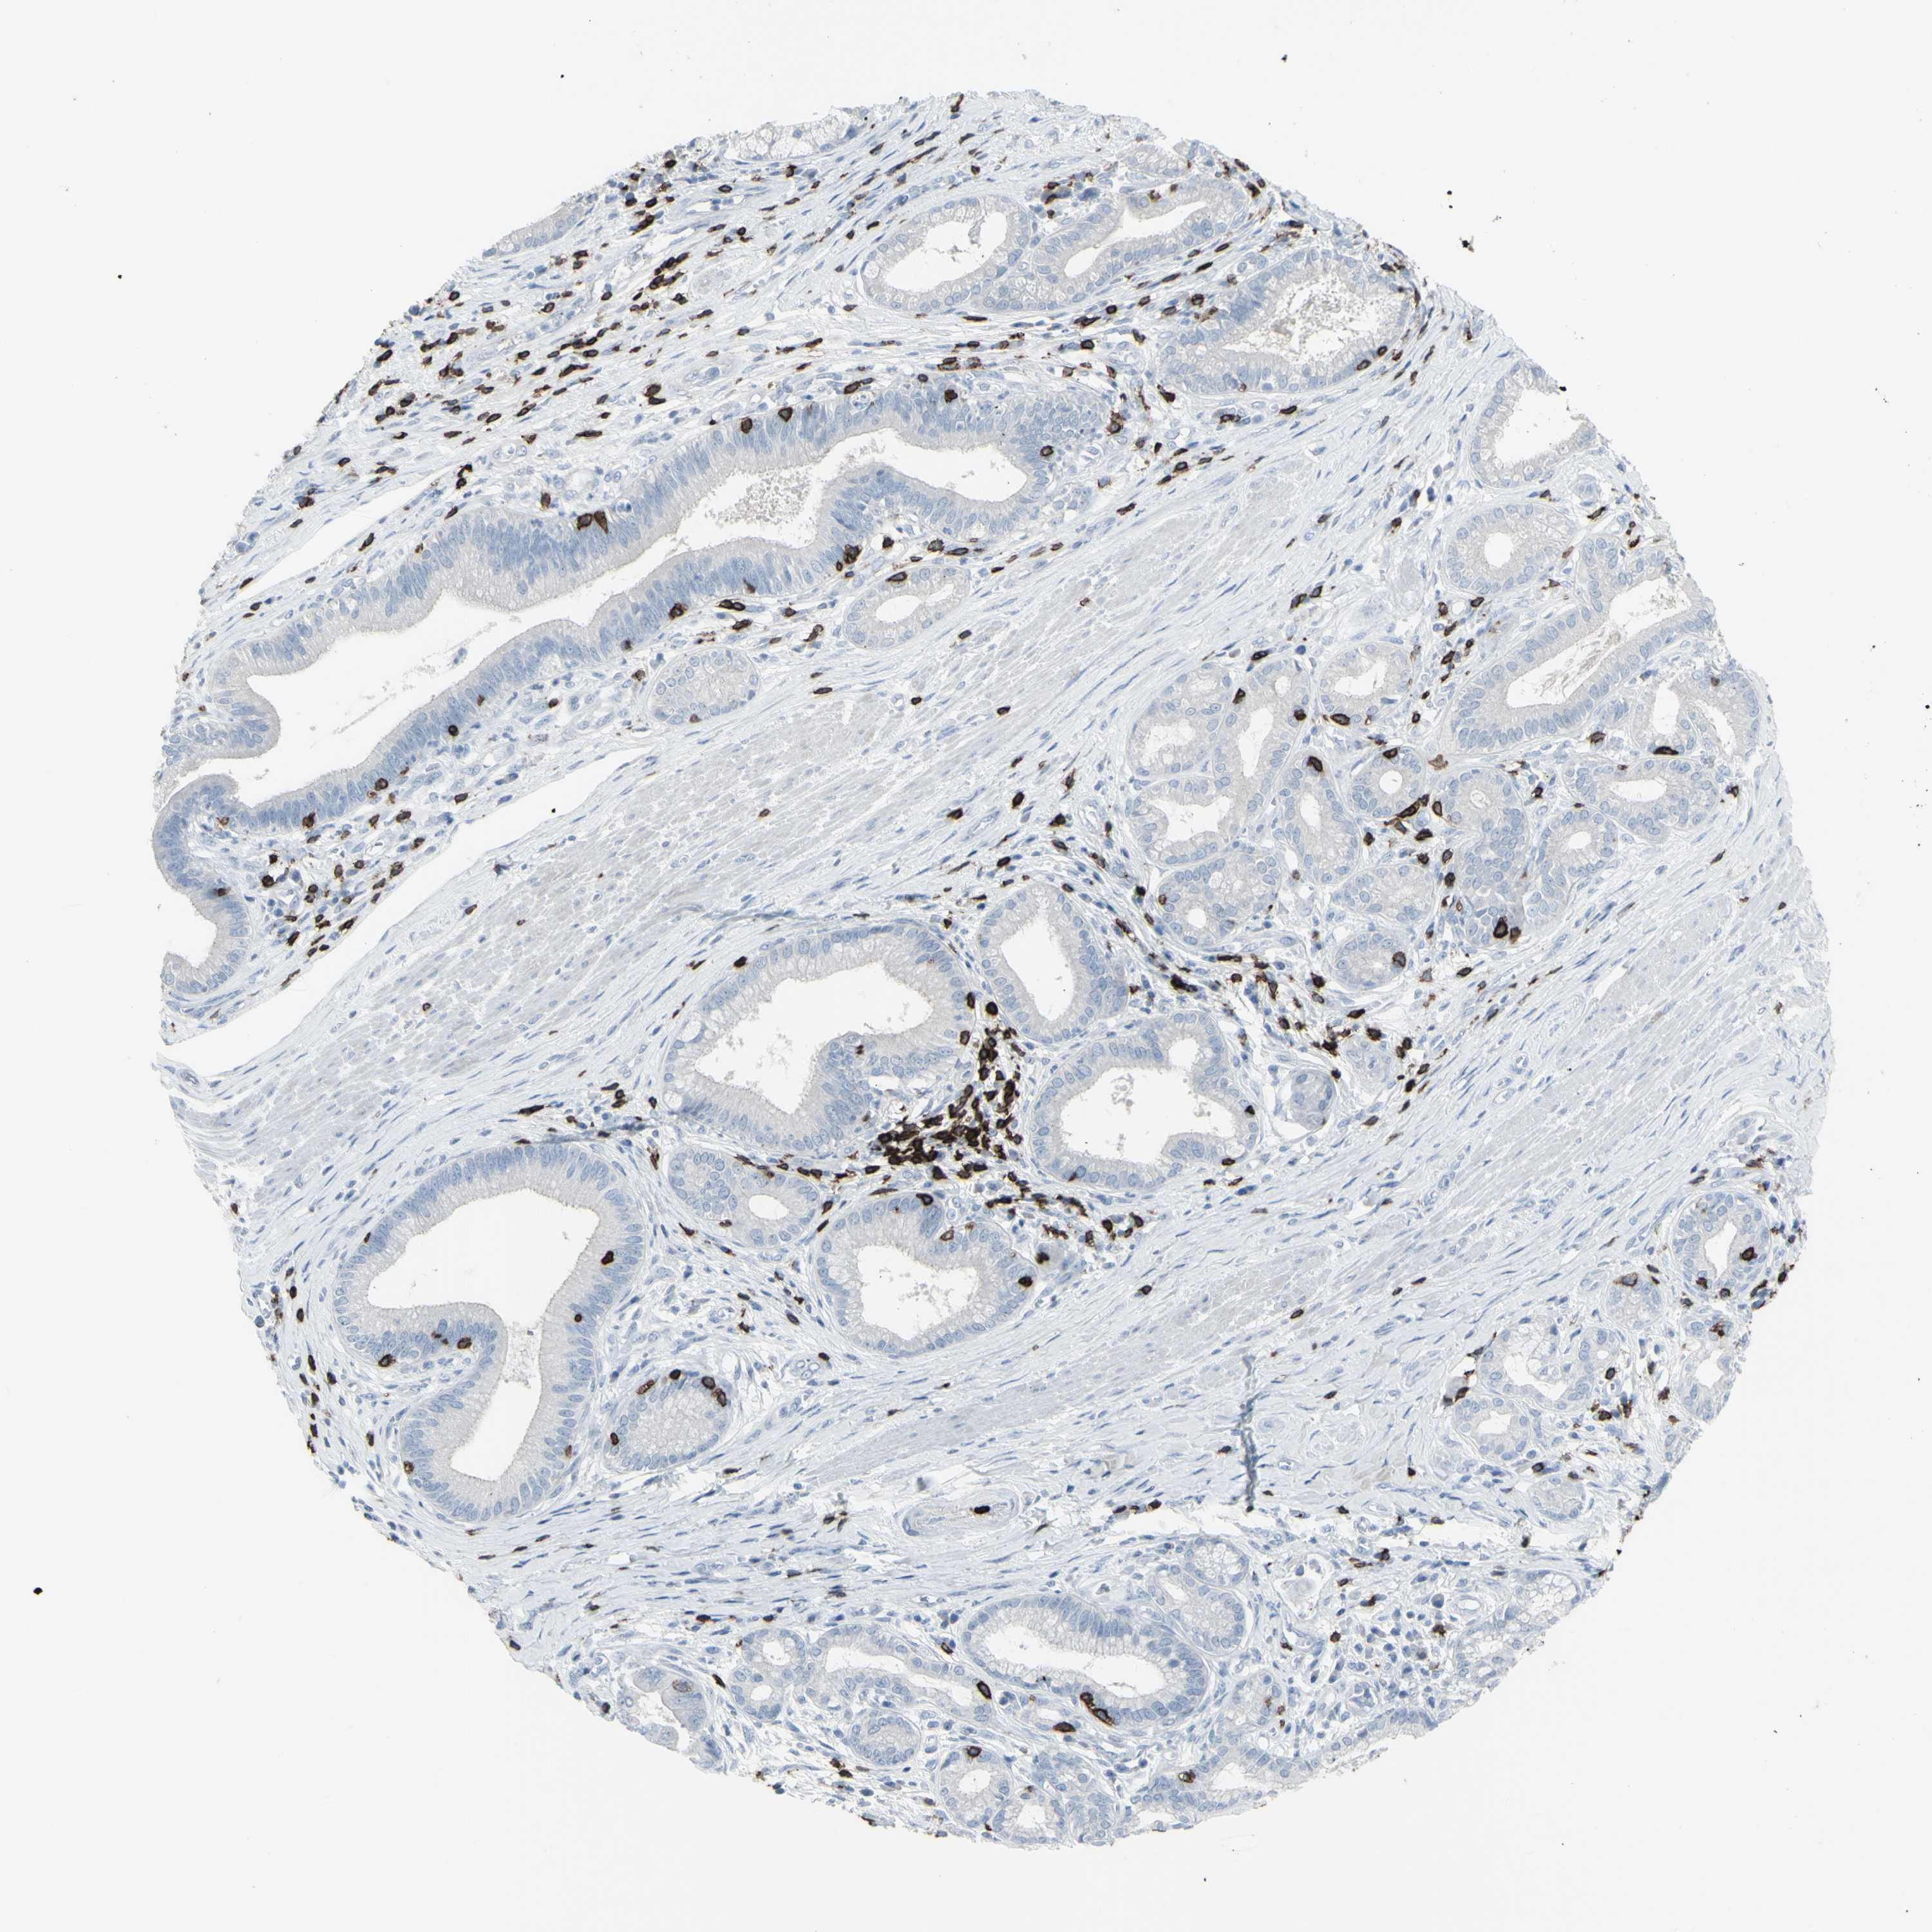

PANCREATIC CANCER - Protein expressioni

A mouse-over function shows sample information and annotation data. Click on an image to view it in a full screen mode. Samples can be filtered based on level of antibody staining by selecting one or several of the following categories: high, medium, low and not detected. The assay and annotation is described here.

Note that samples used for immunohistochemistry by the Human Protein Atlas do not correspond to samples in the TCGA dataset.

Antibody stainingi

Antibody staining in the annotated cell types in the current human tissue is reported as not detected, low, medium, or high, based on conventional immunohistochemistry profiling in selected tissues. This score is based on the combination of the staining intensity and fraction of stained cells.

Each image is clickable and will lead to virtual microscopy that enables deeper exploration of all samples and also displays staining intensity scores, fraction scores and subcellular localization as well as patient and tissue information for each sample.

Antibody HPA008750

Antibody CAB004651

Adenocarcinoma, NOS

Adenocarcinoma, metastatic, NOS